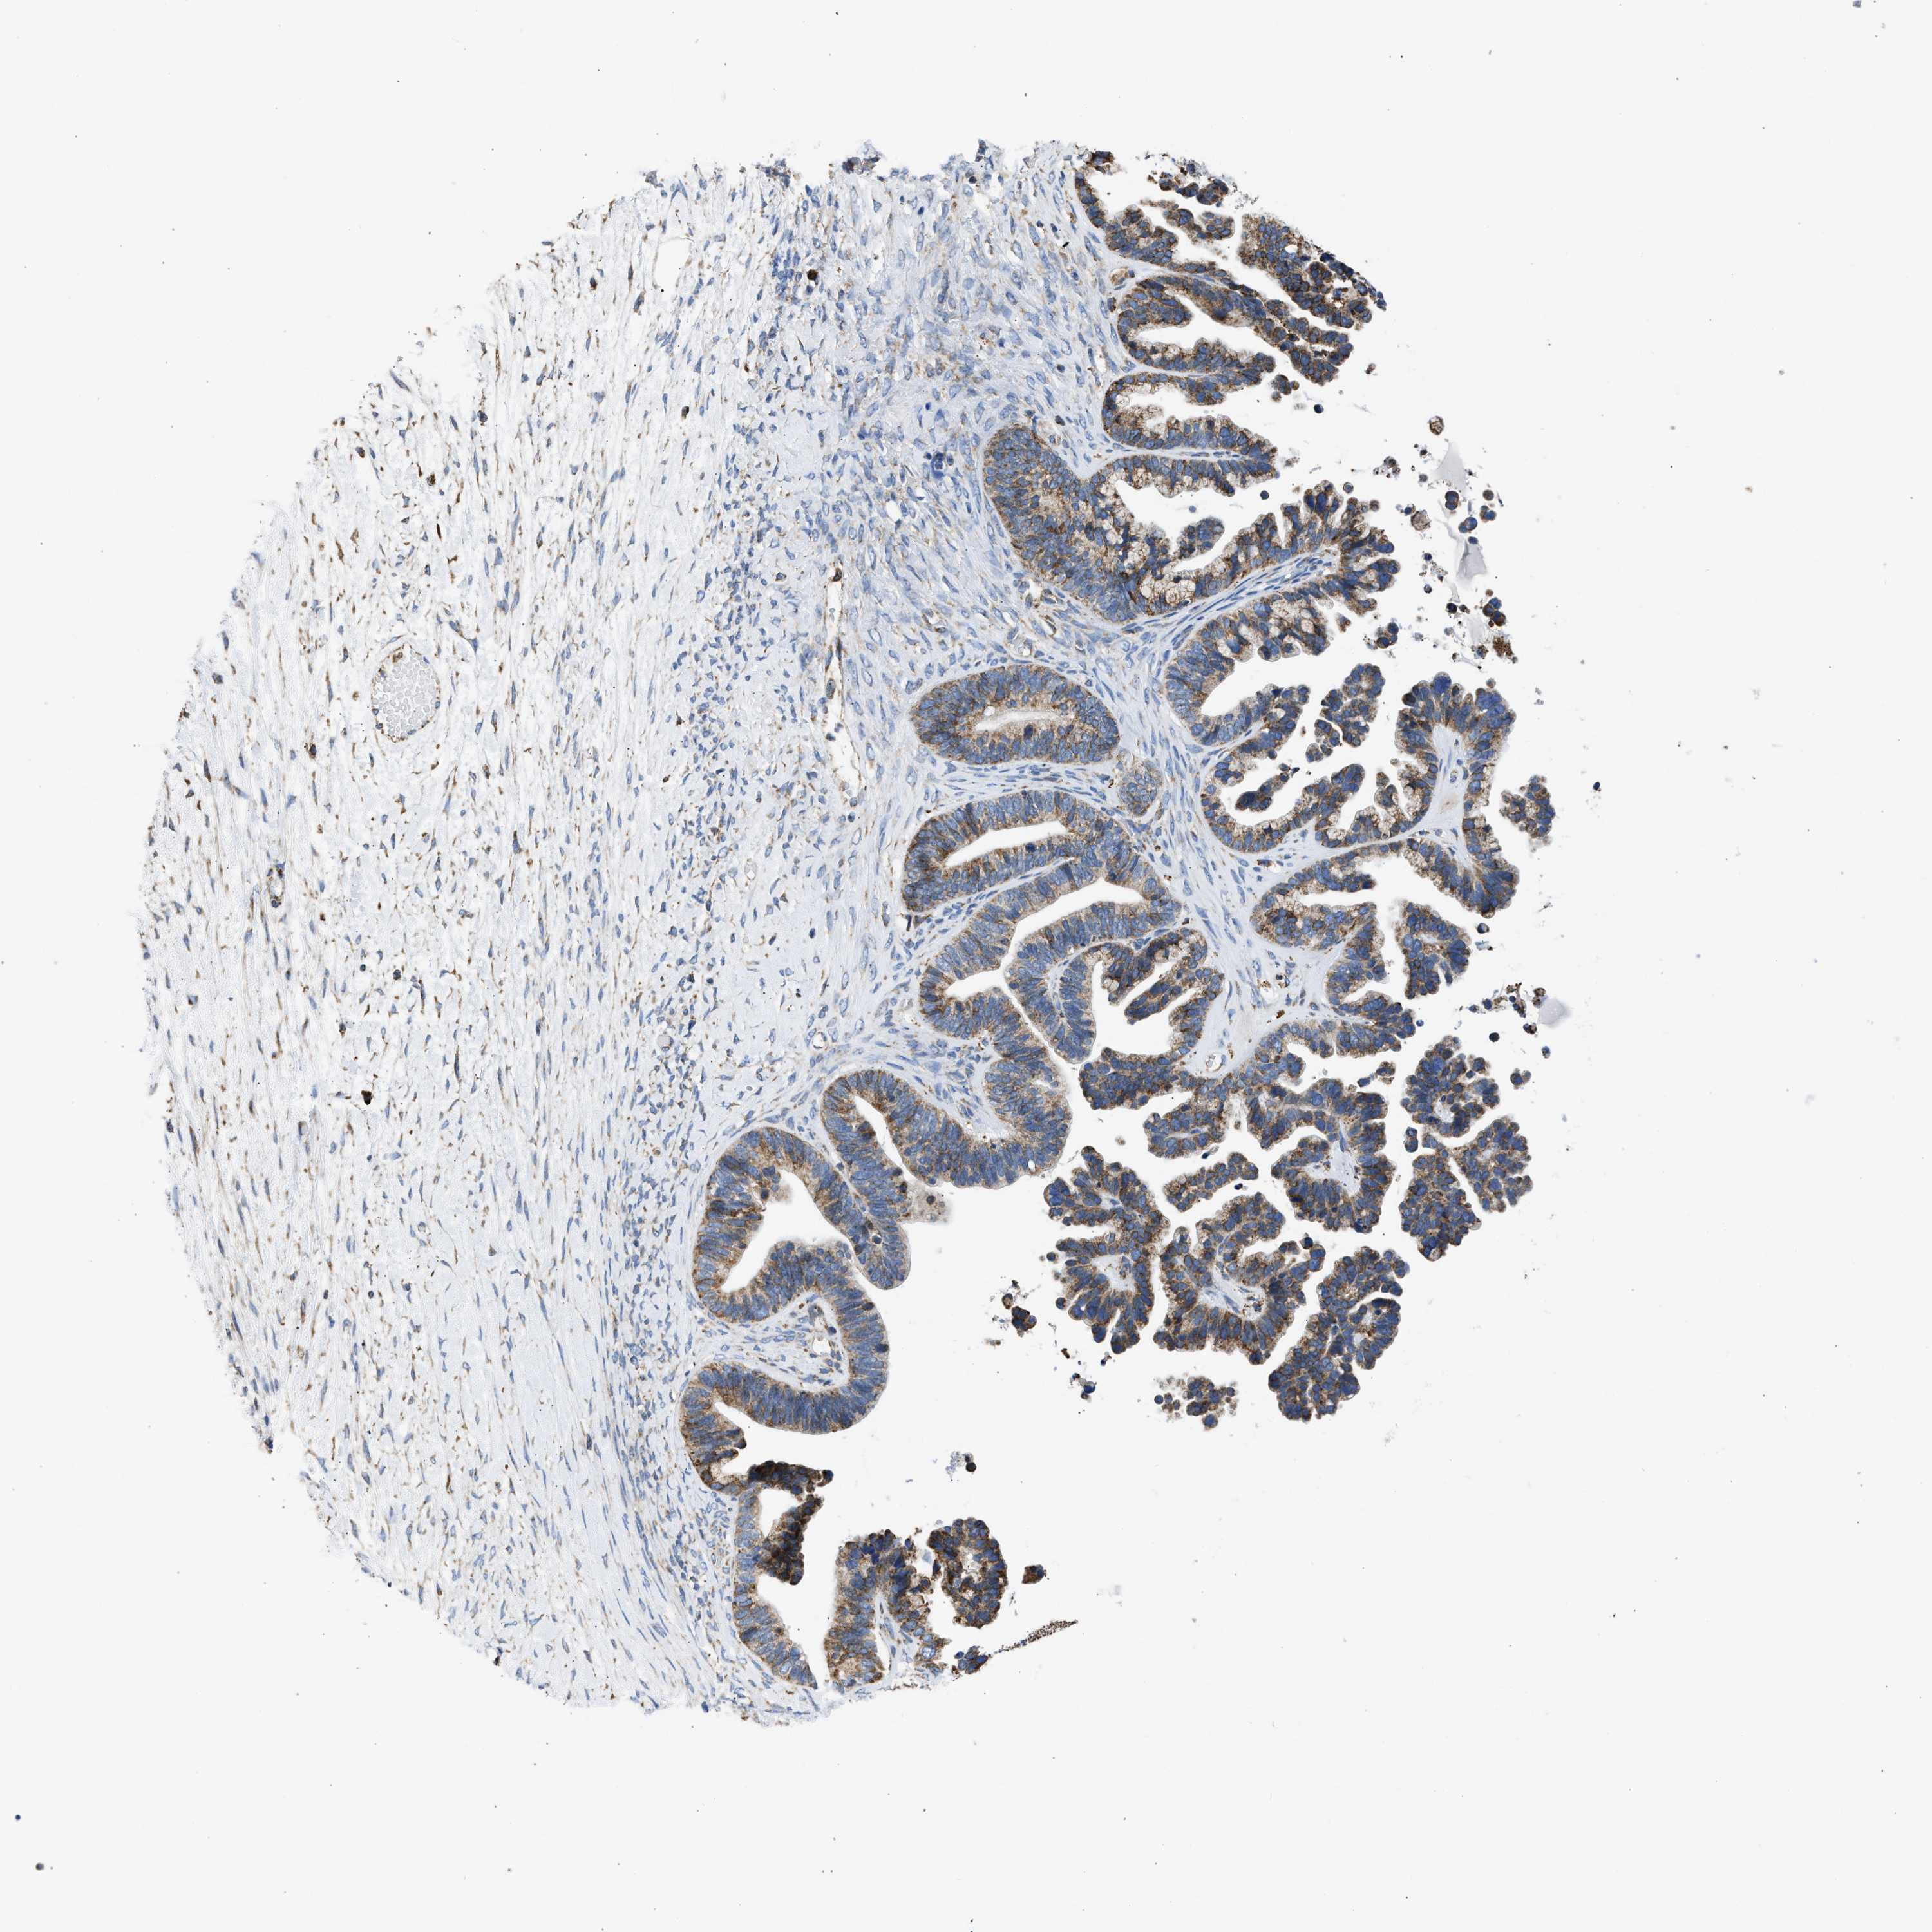

OVARIAN CANCER - Protein expressioni

A mouse-over function shows sample information and annotation data. Click on an image to view it in a full screen mode. Samples can be filtered based on level of antibody staining by selecting one or several of the following categories: high, medium, low and not detected. The assay and annotation is described here.

Note that samples used for immunohistochemistry by the Human Protein Atlas do not correspond to samples in the TCGA dataset.

Antibody stainingi

Antibody staining in the annotated cell types in the current human tissue is reported as not detected, low, medium, or high, based on conventional immunohistochemistry profiling in selected tissues. This score is based on the combination of the staining intensity and fraction of stained cells.

Each image is clickable and will lead to virtual microscopy that enables deeper exploration of all samples and also displays staining intensity scores, fraction scores and subcellular localization as well as patient and tissue information for each sample.

Antibody CAB004222

Antibody CAB005126

Antibody CAB018597

Cystadenocarcinoma, serous, NOS

Cystadenocarcinoma, mucinous, NOS

Carcinoma, endometroid

Carcinoma, NOS